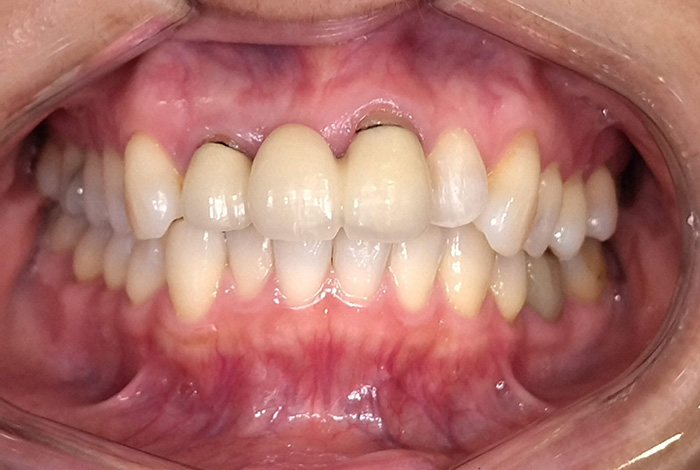

右上臼歯部2本・左下臼歯部2本にインプラント治療を行った症例です。

欠損部に対しインプラントを埋入し、咀嚼機能の回復と咬合バランスの改善を行いました。周囲歯への負担を抑えながら、固定性のある補綴装置により安定した噛み心地を目指した治療です。

Before

After

【右上臼歯部インプラント治療】インプラント埋入手術および上部構造装着(2本)

【左下臼歯部インプラント治療】インプラント埋入手術および上部構造装着(2本)

【右上臼歯部インプラント治療】約4か月

【左下臼歯部インプラント治療】約3か月

【右上臼歯部インプラント治療】8回

【左下臼歯部インプラント治療】8回

【右上臼歯部インプラント治療】1本 ¥555,500(税込)

※本症例は2本

【左下臼歯部インプラント治療】1本 ¥555,500(税込)